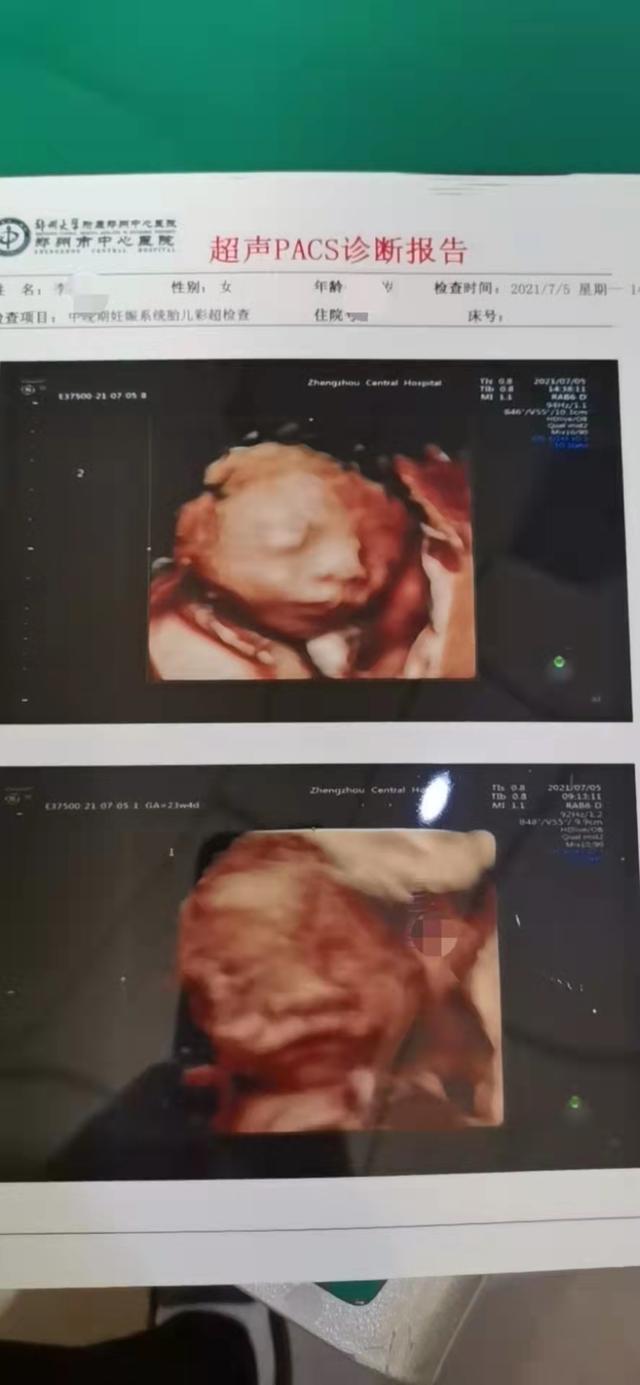

天呀!老天给了我个大惊喜!我要当双胞胎爸爸啦 2021年9月28日 下午8:18 • 生活 老婆去医院做孕检,一直以为是一个孩子,孕检做B超居然怀了两个孩子。 老婆去医院做孕检,一直以为是一个孩子,孕检做B超居然怀了两个孩子。 四维B超拍的照片真是不咋地,看照片的样子完全没有遗传到我的优秀的基因,不会全仿我的缺点了吧[泪奔]。孩子还没见到就已经买了一大堆东西了,小孩子果然都是“吸血鬼”呀。现在真的是好生不好养。努力工作给孩子买奶粉吧[加油] 内容来源网络,如有侵权,联系删除,本文地址:https://www.230890.com/zhan/18817.html [db:标签] 赞 (0) 生成海报 相关推荐 买股票如何了解一家公司,买自己公司的股票靠谱吗 如果你是一个价值投资者,或者你即将走在价值投资的路上,那么你一定要看完全文! 生活 2021年11月28日 罗永浩嘲笑苹果最新文案 连用两个“没文化” 【字谜科技】11月16日,苹果一直以独特的苹果味宣传文案娱乐大众。近期原锤子科技创始人罗永浩显然是看不过眼了,直批苹果iso15的文案:没文化,真是没文化。连用两个没文化,省略号加叹气,还顺带用上了“强得很”的苹果iPhone13 Pro的文案梗。 科技 2021年11月17日 六个月宝宝战胜新冠病毒(告诉孩子新冠病毒有多么可怕) 当父母的人都知道,婴儿容易患上呼吸道感染。婴幼儿的抵抗力比成年人要低许多,没能有足够的抗体让病原体绕道走。但是根据目前的研究数据来看,儿童似乎能免于发展成为新型冠状病毒肺炎重症患者,病毒对儿童的影响不像对成年人那么严重。许多传染性疾病,从常见的水痘和麻疹,到新出现的严重急性呼吸综合征(SARS)和中东呼吸综合征(MERS),都存在类似特点。目前,医生们也并未完全了解这一现象的原因。 生活 2021年12月17日 轻度认知障碍一定会得老年痴呆症吗,轻度认知障碍和老年痴呆有什么区别 轻度认知障碍是一种介于正常衰老和失智(又称认知症、痴呆症)之间的中间状态,研究表明,轻度认知障碍常见于老年人群,随着年龄的增长,患轻度认知障碍的风险会越来越高。 生活 2021年12月5日 马斯克造手机,马斯克的手机 视频加载中... 科技 2021年12月9日 研究发现:这5类食物对心脑血管有好处,可以降低发病风险 心脑血管疾病可以说是严重威胁人们健康的主要杀手,人们也都在这方面采取了各种各样的预防措施,特别是中老年人更是如此,除了适当地进行体育锻炼之外,最主要的就是在饮食方面加以控制了,有些不适合吃的食物就不能再吃了,然而为了使我们的身体更加健康,为了远离心脑血管疾病,我们更可以在饮食上多吃一些有助于预防心脑血管疾病的食物。 生活 2021年9月6日